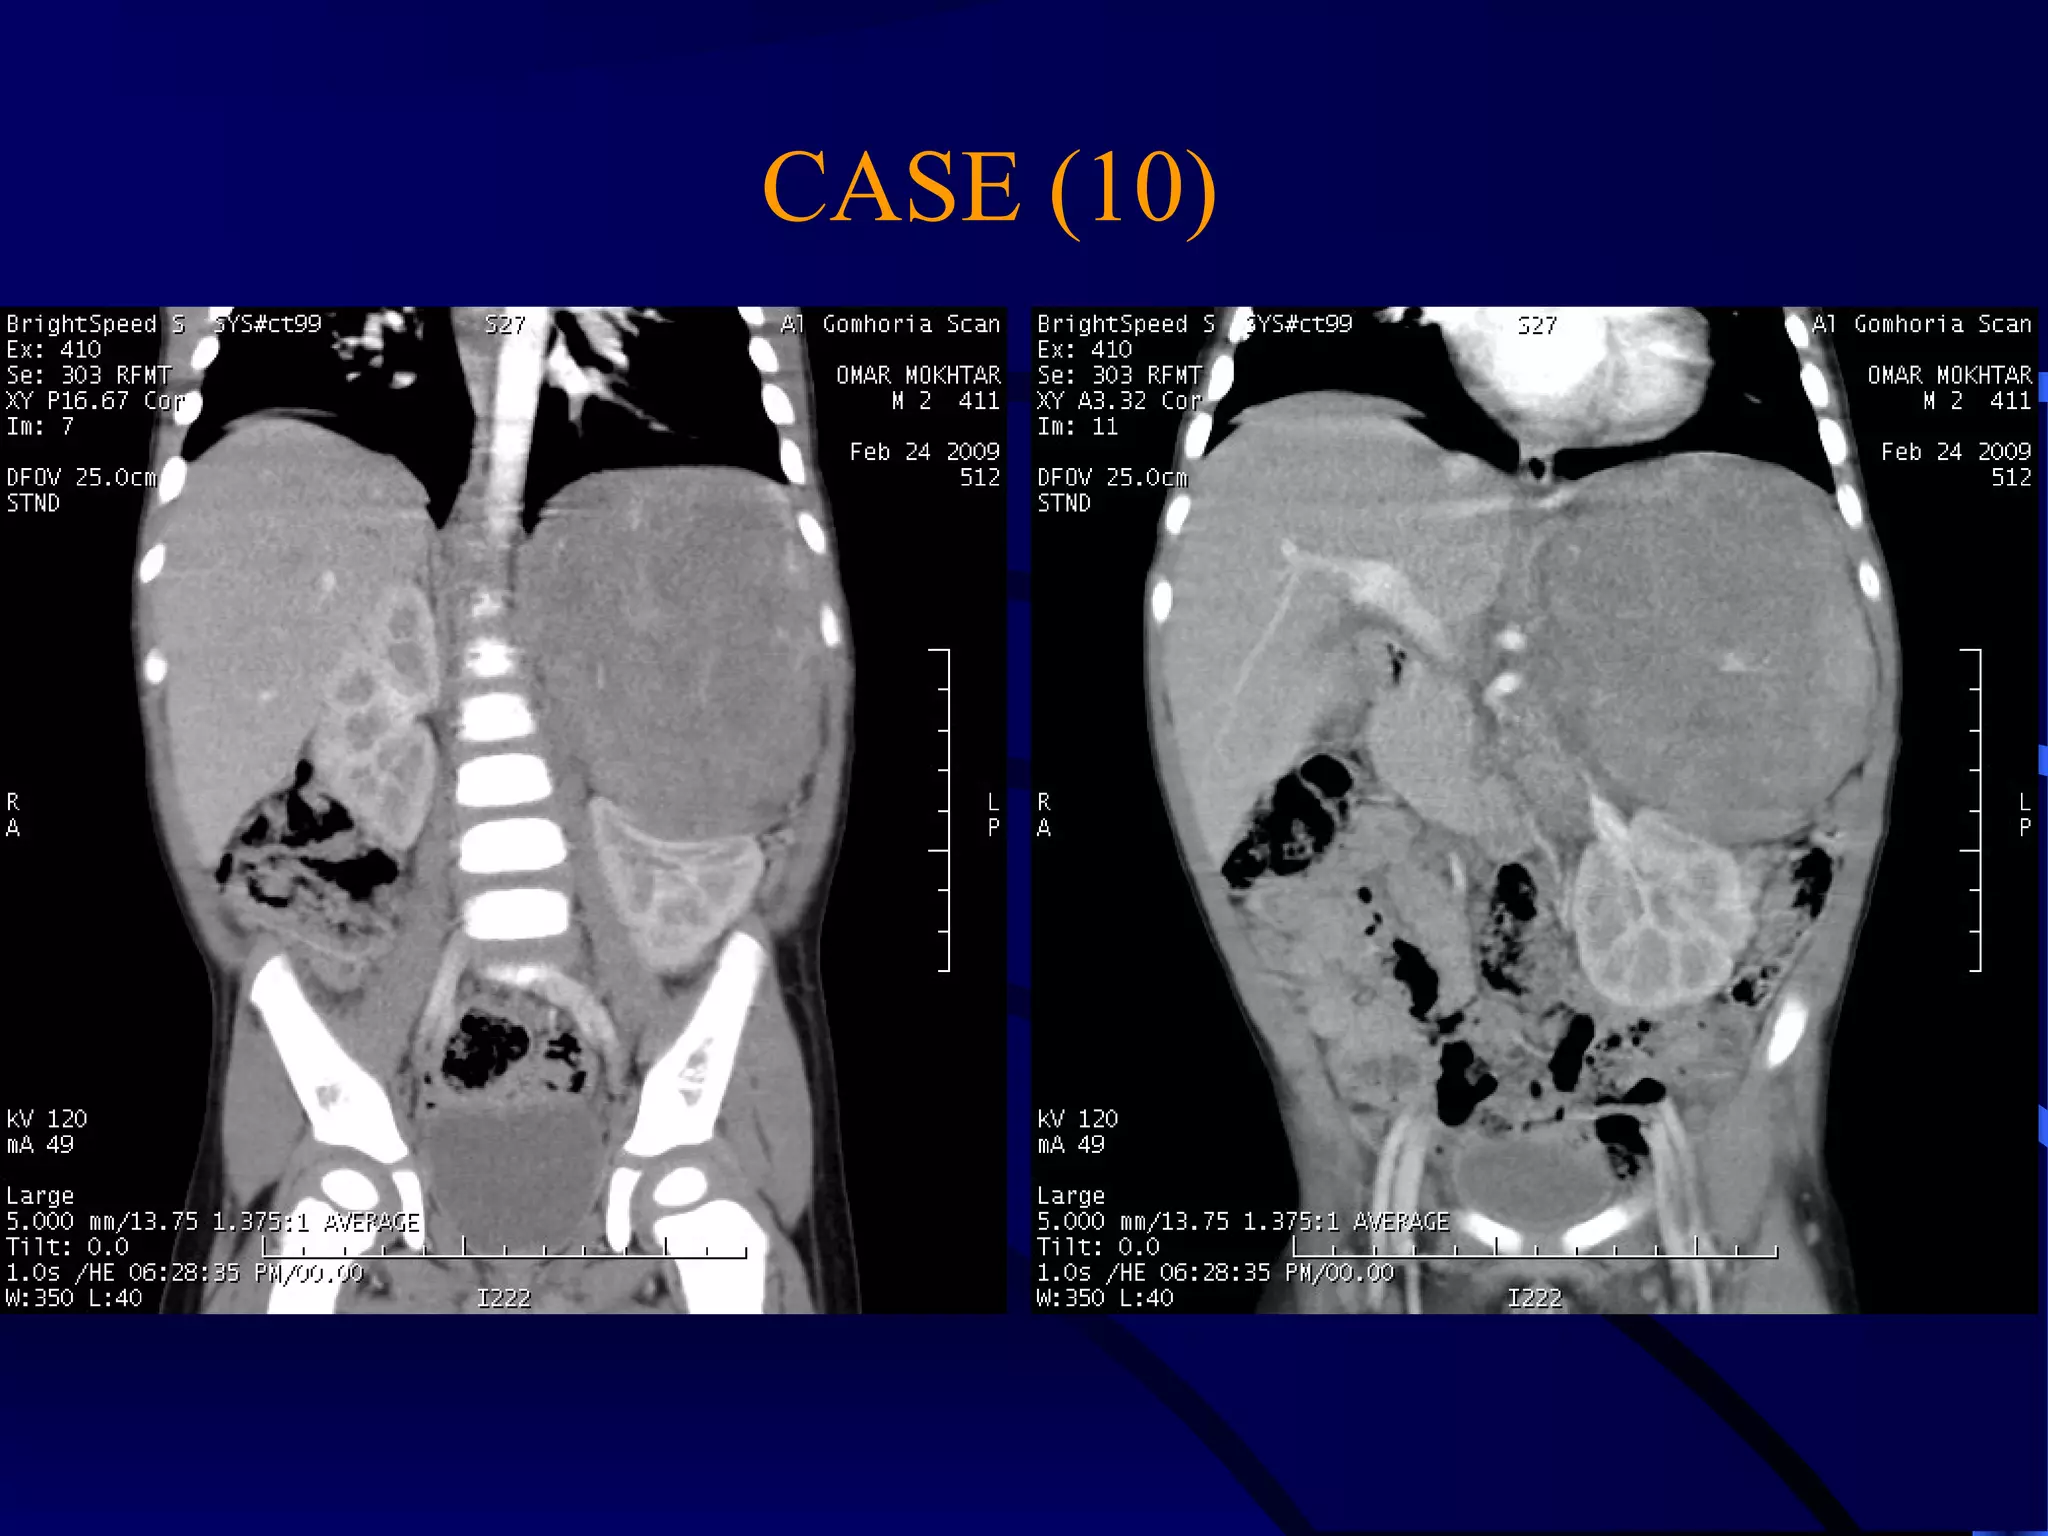

CASE (10)

MALIGNAT SUPRARENAL MASS

WITH LIVER METASTASES

DISPLACED LEFT KIDNEY WITH

DOUPLEX RIGHT COLLECTING SYSTEM